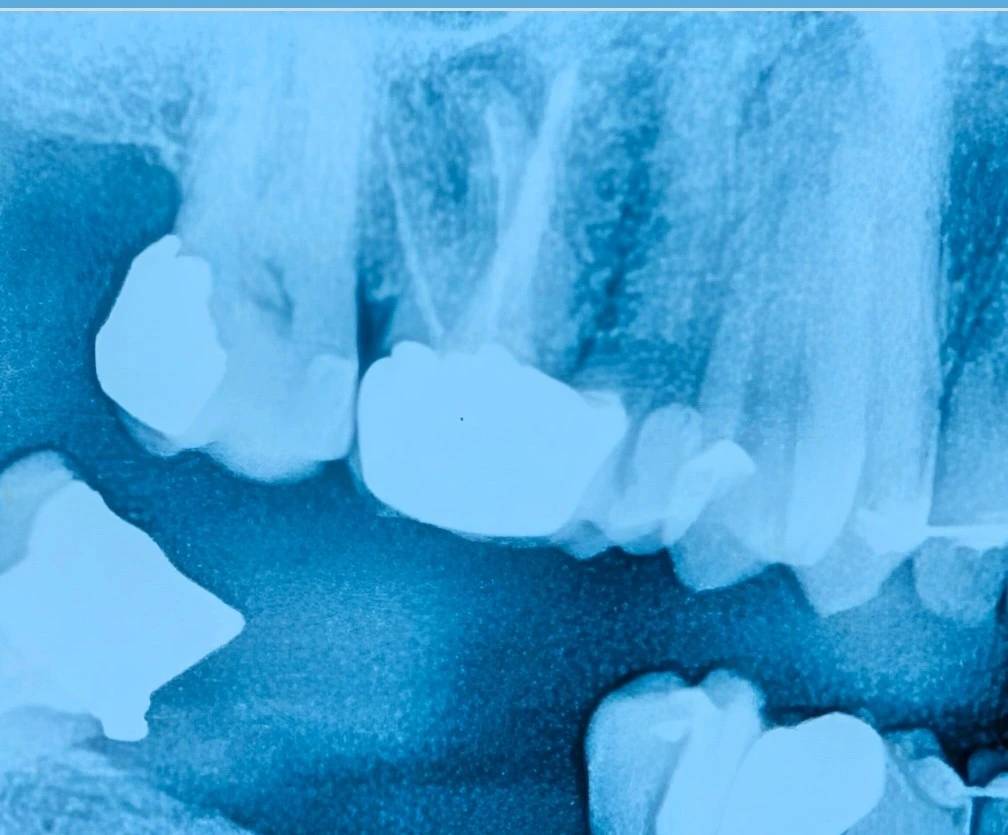

بیمار برای طرح درمان دندان ۶ بالا سمت راست مراجعه کرده بود. این دندان دارای روکش بود و در عین حال شواهدی از مشکلات زیرین—از جمله نیاز به درمان مجدد ریشه—وجود داشت.

در این کیس، پیش از هر تصمیم قطعی، روکش قدیمی خارج شد و تمام پوسیدگیها و ترمیمهای قبلی بهطور کامل حذف شدند.

این مرحله یک اکسپوژر واقعی از وضعیت دندان ایجاد میکند.

در صورت نیاز، پس از این اکسپوژر واقعی تصویربرداری مجدد انجام میشود تا ارزیابی دقیقتری از وضعیت ریشه و ساختار باقیمانده به دست آید.